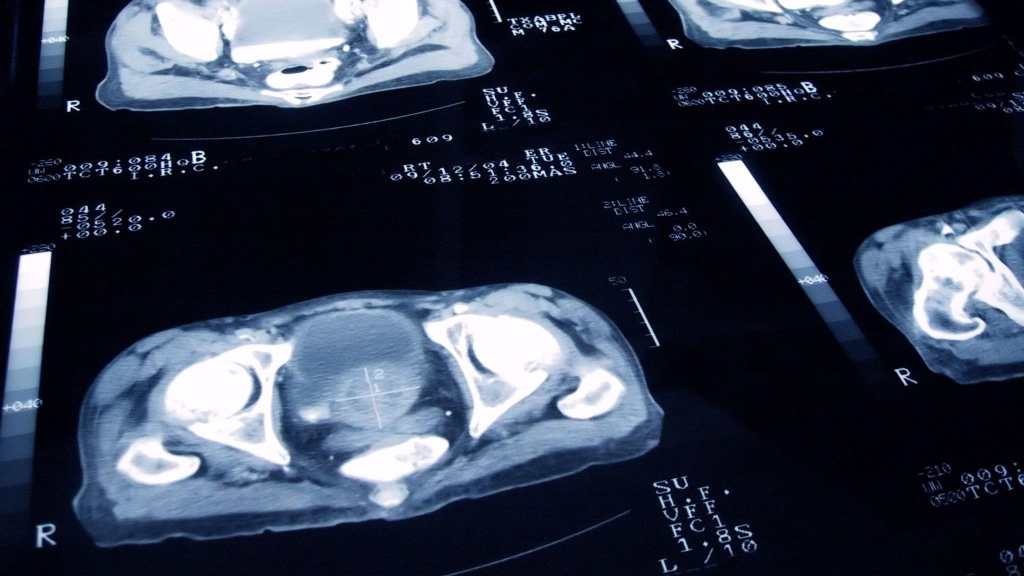

Cáncer de mama: ¿Cuáles son los tipos más frecuentes y los tratamientos a seguir?

Uno de los procesos más importantes es reconocer el tipo de cáncer de mama que padece la paciente para recibir el mejor tratamiento.

El diagnóstico de cáncer de mama representa un cambio para la paciente y su familia. Las evaluaciones, exámenes y procesos están llenos de resultados y a veces estos se encuentran en un lenguaje que no es conocido.

La médica Sonia del Barco, especialista en oncología médica, comenta que el cáncer de mama es el tumor maligno más frecuente en la mujer y se le llama con frecuencia entre los médicos como carcinoma de mama.